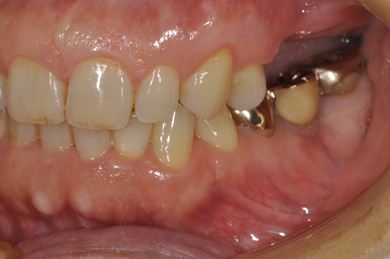

| 性別/年齢 | 女性 / 59歳 | ||||||||||||||||||||||||||||||||

| 主訴 | 奥歯がないので、インプラントか入れ歯の相談をしたい。 | ||||||||||||||||||||||||||||||||

| 治療方針 | 左上奥ソケットリフトにて上顎洞を拳上、骨再生法を行い、インプラント治療を可能にする。 | ||||||||||||||||||||||||||||||||

| 治療内容 | インプラント4本(GBR)、ハイブリッドセラミック4本 | ||||||||||||||||||||||||||||||||

| 総治療費 | 1,680,000円 | ||||||||||||||||||||||||||||||||

| 治療期間 | 11ヶ月 |